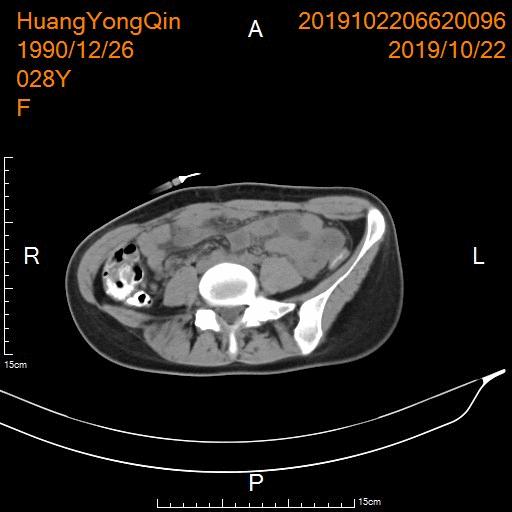

- 介入硬化治疗后复查CT显示囊腔已基本消失。